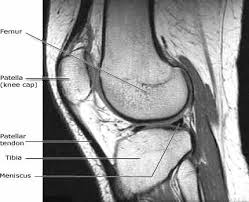

The mri can take between 20 minutes and 1 hour, depending on the body part. A doctor is trained for over 11 years (many specialists are trained even longer) to make the right decisions on behalf of patients. Mri results are usually available to a doctor within one to two days, reports webmd. An mri scan can take between 15 to 90 minutes depending on which part of your body needs to be scanned. An mri exam is a painless procedure. Most knee mri scans take about 30 minutes,. If someone urgent is found, they will usually get an urgent notification. A knee mri (magnetic resonance imaging) scan uses energy from strong magnets to create pictures of the knee joint and muscles and tissues.

Leave time for filling out paper work and getting dressed for the scan as well. During your mri, you'll hear loud noises like thumping and tapping as the machine goes to work. 1  it works by creating a magnetic field that causes the water molecules in tissue, bones, and organs to orient themselves in different ways. How long does an mri of the knee take to do? There are no known harmful effects from the strong magnetic field used for an mri. Mri results can take days or weeks depending on how comprehensive the scans were. The test most often lasts 30 to 60 minutes, but may take longer. We scan axial (top to bottom) sagittal (right to left) and coronal (front to back). Diagnostic radiology 42 years experience. These orientations are then translated into images we can use for diagnosis. Meet scott, a technologist for michigan residence imaging. In other cases, it might take a few days. But the magnet is very powerful.